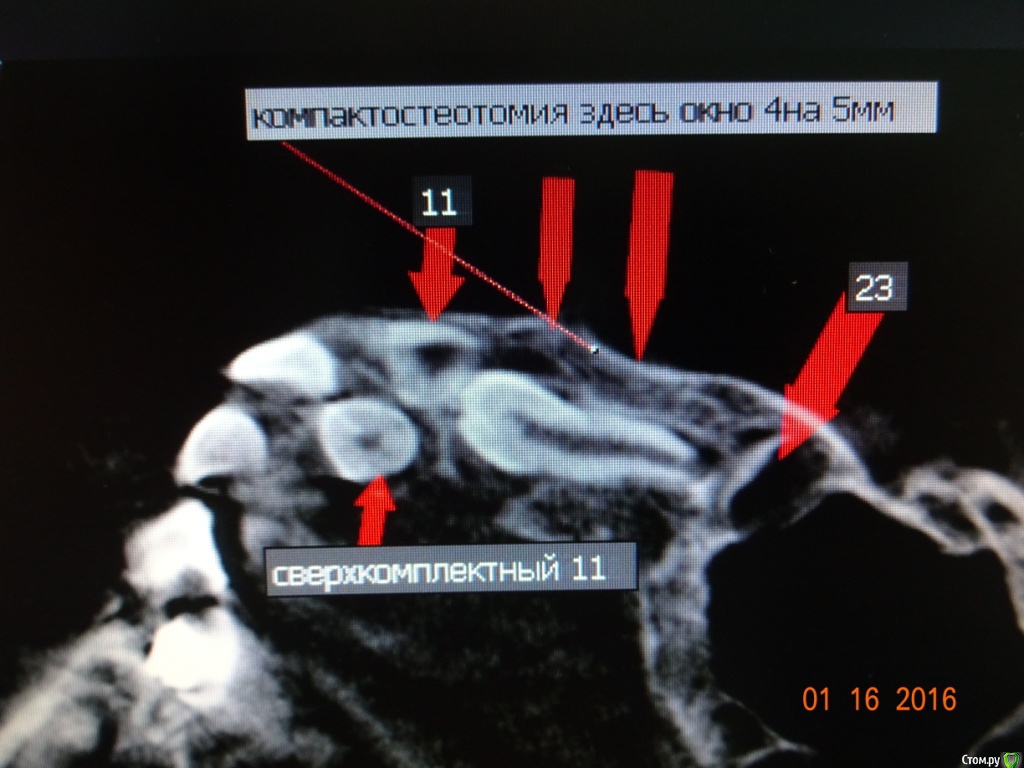

Dok22 Опубликовано 21 января, 2017 Поделиться Опубликовано 21 января, 2017 Это фотоаппарат врет, вмешательство от 4.01.2017. Родители получили инструкции+скайп ждем.Док не надо бояться начните с простого,кто если не мы? Делал так :1) Перед вмешательством седация.Анестезия.2) Вырезал лоскут с надкостницей, создав окно примерно 1кв.см.(чтоб не бороться с краями раны, я так и 8 убираю)3) Компактостеотомия ультразвуковым алмазом(кость мягкая режется легко ,им же режем сверхкомплектный зуб бывает вертится в ране можно фиксировать гладилкой)4) Сегментируем зуб,выбираем фрагменты(обязательно тщательно убрать ростковую капсулу сверкомлектного,обильно промыть водой.Аккуратно проконтролировать отсутствие ростковой зоны!!!)5) Рана не ушивается, только тампонада как при обычном удалении.6) Инструкции родителям(отеки,субфебрильная температура,болезненность это нормально не более суток,при болях детское) Вам нужен ассистент,тонкий кровоотсос,обычный слюноотсос,тонкий элеватор(3-4милиметра) и самое важное ТЕРПЕНИЕ.Спрашивайте. 1 Ссылка на комментарий